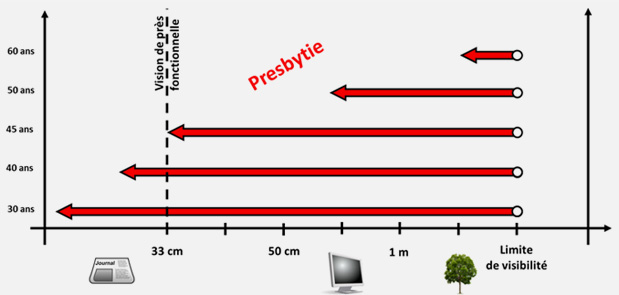

La presbytie est un trouble de la vision lié à l'âge, correspondant à la diminution progressive de la capacité d'accommodation de l'oeil. Elle est généralement associée à une difficulté à voir de près.

L'accommodation est le mécanisme permettant à l'oeil de voir à plusieurs distances. Ce mécanisme repose sur la capacité du cristallin à se déformer et à ajuster sa puissance.